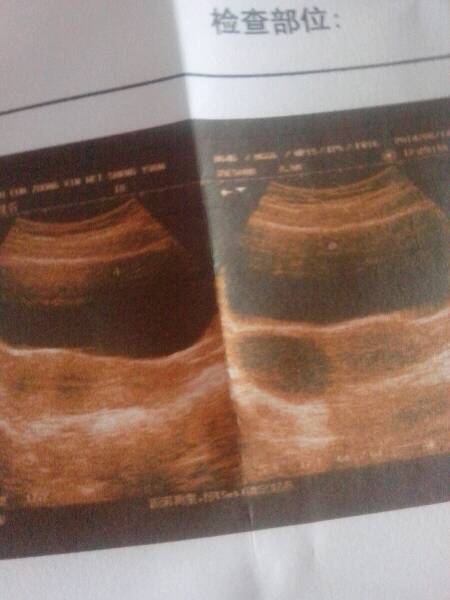

谁能告诉我为什么不见孕囊?我去把脉人家说我怀孕了,这是为什么啊

现在需要抽血检查下,确定HCG的分泌水平,确定是否怀孕,如果怀孕,在孕45天后可以行B超检查到孕囊的。现在的症状比较正常。